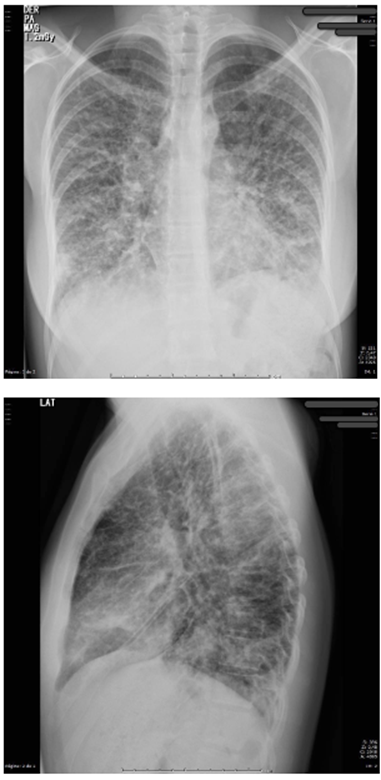

Se contaba con radiografía de tórax tomada en otra institución en la que se documentaron extensas opacidades parenquimatosas mixtas y ocupación alveolar, involucrando predominantemente los lóbulos inferiores, correspondiente a edema pulmonar evolutivo de origen no cardiogénico. Se decidió tomar tomografía computarizada de tórax de alta resolución (TCAR) (figura 1), cuyos hallazgos anormales se reportaron como consolidaciones bibasales confluentes y en lóbulo medio por probable neumonía multilobar y consolidaciones en lóbulos superiores; no se identificaron masas pulmonares ni derrame pleural, lo cual era concordante con la impresión diagnóstica inicial de neumonía.

Figura 1. Tomografía de tórax de alta resolución con imagen de consolidaciones bibasales confluentes.

Se decidió realizar una tomografía de abdomen (figura 3) que mostró engrosamiento concéntrico de las paredes del colon sigmoide de 7 mm de espesor, de aspecto inespecífico, de probable etiología inflamatoria, asociado a coprostasis en el colon ascendente y transverso, sin observarse adenomegalias, y endoscopia de vías digestivas altas, cuyo único hallazgo fue gastritis crónica. En la radiografía de tórax de control (figura 4) se aprecian cambios dados por opacidades reticulares bilaterales en 4 cuadrantes y aumento del proceso reticular previo, por lo que se hace necesario la toma de biopsia pulmonar por parte de cirugía de tórax.

Figura 4. Radiografía de tórax proyección AP y lateral con opacidades reticulares bilaterales en 4 cuadrantes.